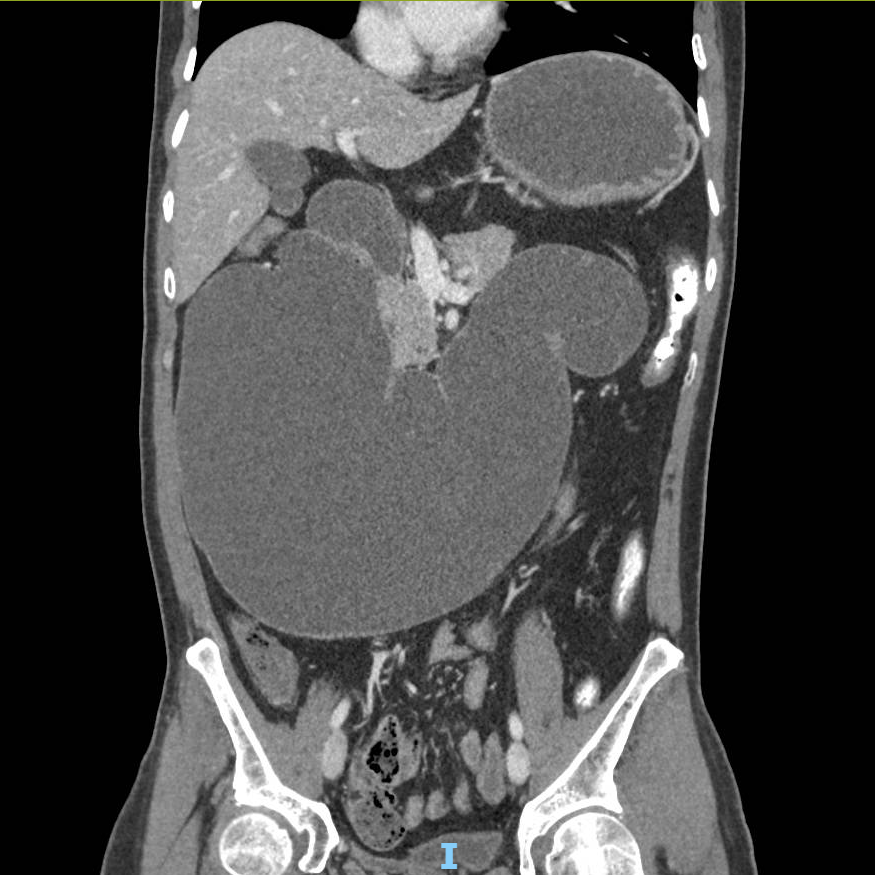

Kết quả chụp cắt lớp vi tính (CT scan) cho thấy, dạ dày và tá tràng giãn cực đại, chiếm gần toàn bộ khoang bụng. Bệnh nhân được hồi sức tích cực, truyền máu và ổn định huyết động. Khi đặt ống thông dạ dày, các bác sĩ đã hút ra hơn 5 lít dịch ứ đọng trong dạ dày và tá tràng của người bệnh.

Hình ảnh chụp cắt lớp vi tính: Tá tràng giãn khổng lồ chiếm gần hết khoang bụng. Ảnh: BV

Bác sĩ Thái cho biết, tá tràng vốn chỉ dài khoảng 25cm, ở trạng thái bình thường có kích thước tương đương ngón tay và chỉ giãn nhẹ khi thức ăn đi qua. Riêng ở bệnh nhân này, tá tràng giãn "khổng lồ" với đường kính lên tới 12cm, chu vi 38cm to như một ống tay áo, gần như chiếm trọn ổ bụng và mất hoàn toàn chức năng co bóp, khiến thức ăn bị ứ đọng kéo dài, không thể xuống ruột non.